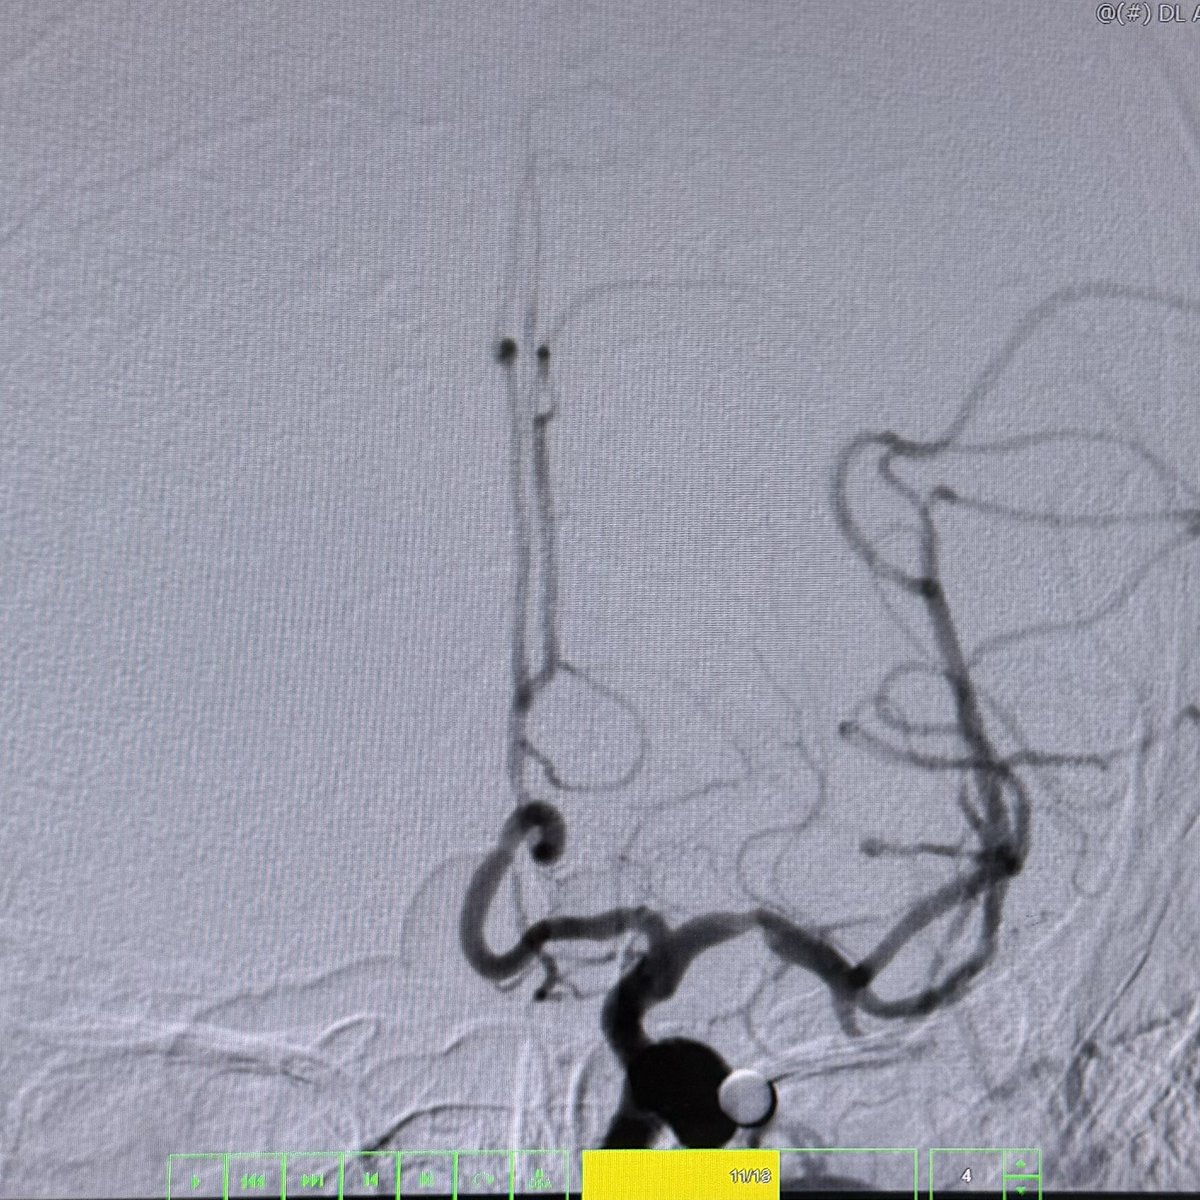

@bobvarkey @PascalJabbourMD given the SAH presentation, matching location, and size exceeding 3 mm, I'd treat this as a ruptured aneurysm and proceed with endovascular coiling ASAP

This 🧔♂️ presents with a subarachnoid haemorrhage in the left suprasellar cistern

DSA shows an infundibulum/ aneurysm of the left PCom. To coil or not was a conundrum. Every expert has a different take

The size is 3.4 mm x 2.6 and it is located in the region of the bleed.

What would you do?